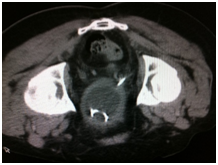

The first and most clinical and cost effective diagnostic tool are urine analysis and ultrasound (Figure 5). CT scan might be used later for further evaluation (Figure 5).

Figure 5 Urothelial cancer in different modalities.